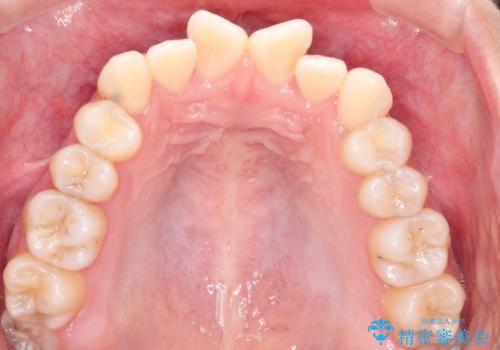

インビザラインによる非抜歯矯正 ガタガタな歯並びを整った歯並びへ

- 前歯のガタガタを主訴に来院されました。

抜歯矯正も考えられる状態でしたが、非抜歯矯正を希望されました。

使用時間を守っていただけたので、スムーズに治療を終わることができました。